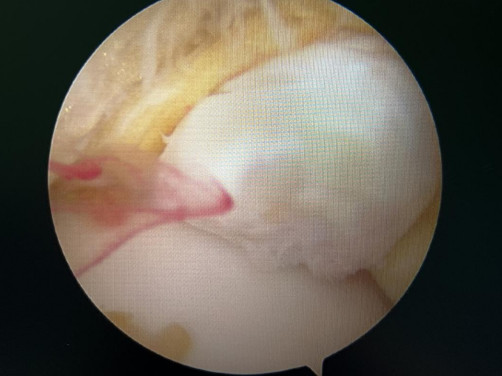

修復(fù)斷裂的韌帶

踝關(guān)節(jié)鏡見前方長骨刺

醫(yī)生們在手術(shù)中發(fā)現(xiàn),李先生的右踝關(guān)節(jié)軟骨損傷明顯,踝關(guān)節(jié)前方及內(nèi)外側(cè)均有不同程度的骨質(zhì)增生,相互撞擊引起疼痛,同時距腓前及跟腓韌帶斷裂。手術(shù)醫(yī)生利用磨鉆,小心翼翼將引起撞擊的骨刺一一去除,然后,修復(fù)了損傷的關(guān)節(jié)軟骨,最后,為他完成了距腓前和跟腓韌帶的修復(fù)。